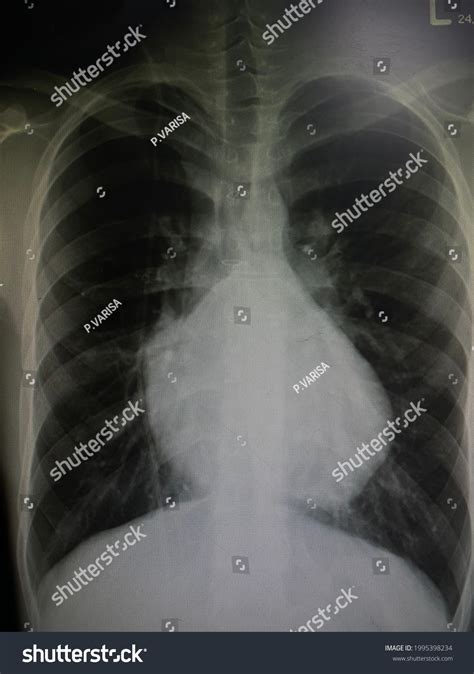

A boot shaped heart is a rare congenital heart defect where the heart takes on an unusual shape, resembling a boot. This condition is often associated with other cardiac abnormalities and can significantly impact an individual's health and quality of life. Understanding the anatomy and physiology of a boot shaped heart is crucial for medical professionals and patients alike.

The heart is a complex organ responsible for pumping blood throughout the body. In a boot shaped heart, the chambers and valves may be malformed or misaligned, leading to various complications. The most common issues include:

• Ventricular Septal Defect (VSD): A hole in the wall separating the heart's lower chambers.

• Atrial Septal Defect (ASD): A hole in the wall separating the heart's upper chambers.

• Pulmonary Stenosis: Narrowing of the pulmonary valve, which controls blood flow from the heart to the lungs.

• Aortic Stenosis: Narrowing of the aortic valve, which controls blood flow from the heart to the rest of the body.

These defects can cause blood to flow inefficiently, leading to symptoms such as shortness of breath, fatigue, and cyanosis (a bluish discoloration of the skin due to lack of oxygen).